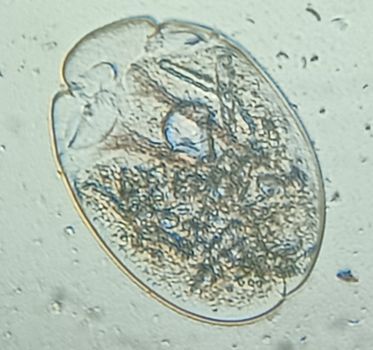

I am Dr.S.Meignanalakshmi, working as Professor, at the Directorate of Centre for Animal Health Studies, TANUVAS, Chennai-51. Working on Foldscope project on "Foldscope for diagnosis of Rumen Acidosis and parasitic infections in cattle" sanctioned by DBT